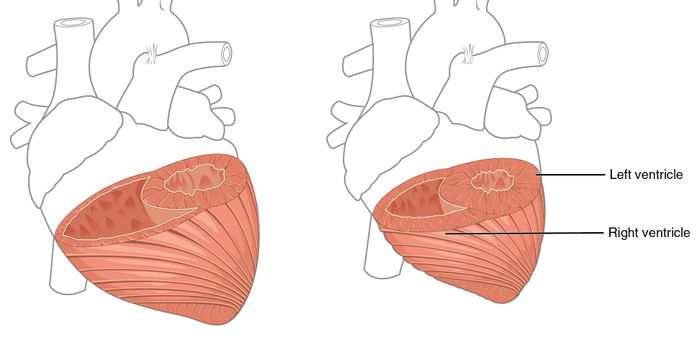

FEB 09, 2017CardiologySometimes a heart attack leads to heart failure later in life, and sometimes it doesn’t. Scientists are concentrat ...

NOV 02, 2016CardiologyA large study of nearly two thousand patients with left main coronary artery disease (LMCAD) has confirmed to scientists ...

MAY 11, 2018CardiologyDuring recovery from a heart attack, the danger is far from over. In a new study from scientists at the University of Bo ...

MAY 30, 2017CardiologyWhat happens during development to create the most common congenital heart defect, a bicuspid aortic valve (BAV)? The id ...